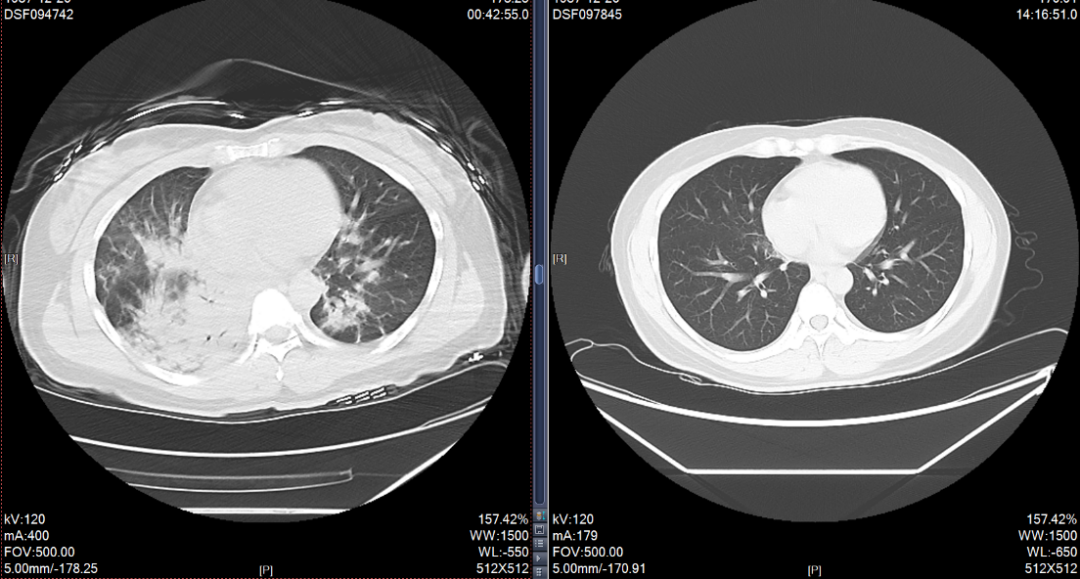

6小时后CT立即出现双肺大面积肺炎 |

为抢救患者生命、减少出现并发症进而影响今后生活质量风险,蒋主任要求紧急收治患者入病房,做好各项术前准备工作。排除禁忌后,立即安排气管镜下冲洗治疗,灌洗出大量脓性分泌物,后续给予足疗程抗感染治疗。4天后,复查患者气管镜示管腔内脓性分泌物完全吸收,一周后,复查CT示肺炎完全吸收。